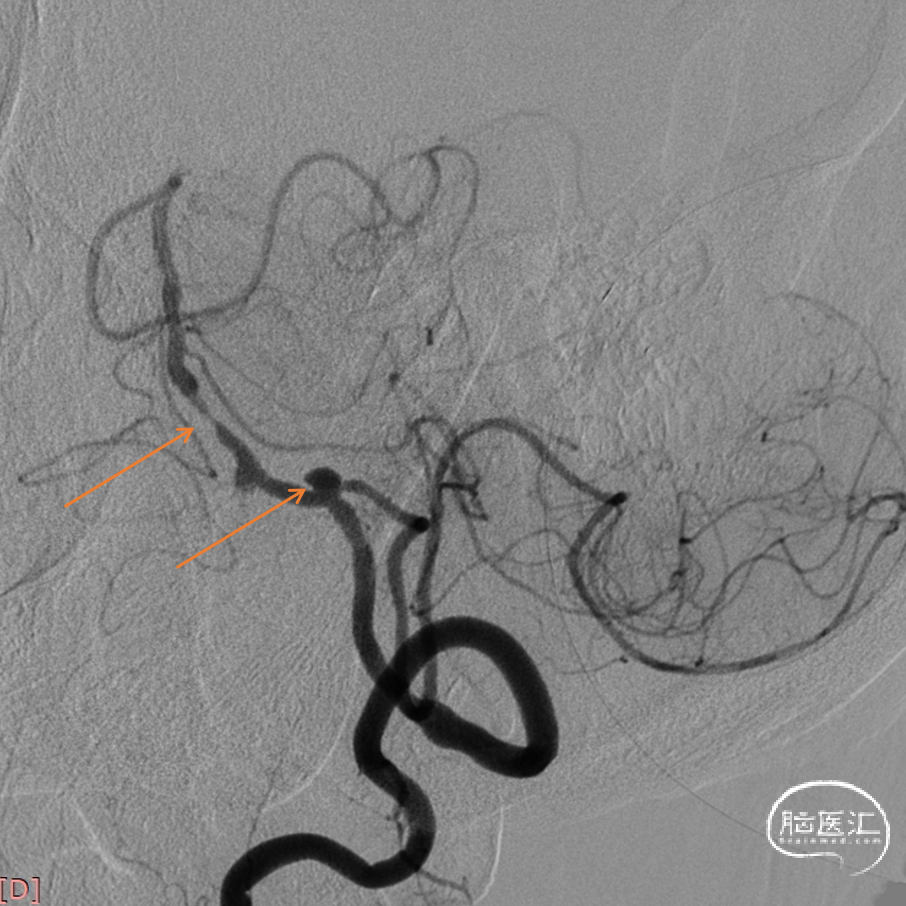

在微导丝引导下,2.0mm*15mm 加奇Fastunnel®输送型球囊扩张导管顺利越过基底动脉狭窄段。

2.0mm*15mm 加奇Fastunnel®输送型球囊扩张导管在狭窄部位以6atm命名压扩张后,沿着Fastunnel®原位释放4.0*23 Enterprise支架。

支架释放。

术后造影。